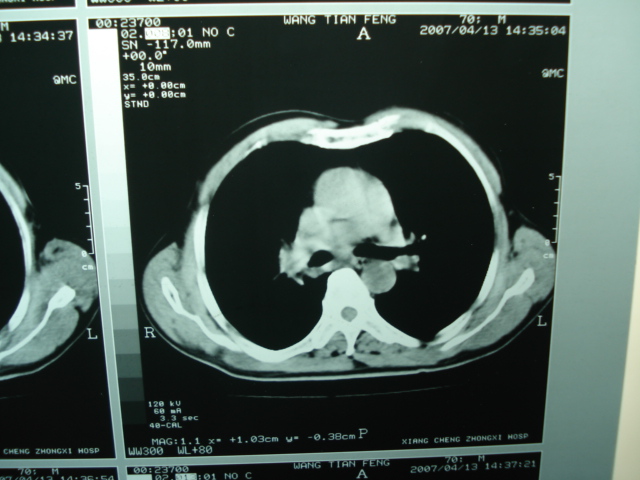

以下是引用狙击手在2007-4-18 20:17:00的发言:[br]原:2007/1/22号ct片:右肺上叶可见片状、云雾状高密度影,右肺上叶后段可见三角形高密度影,尖端指向肺门,右肺上叶后段支气管壁不规则增厚,管腔不规则增厚,纵隔未见肿大淋巴结.[br] 今ct:右肺上叶片状影增大,右肺上叶后段不张及右肺上叶后段支气管壁不规则增厚未见变化,右肺下叶背段支气管壁不规则增厚.[br] 如果考虑肺结核,但从临床证据看竟然没有一项支持肺结核,不知患者是否已经过正规抗结核治疗。没有的话,3个月了前后片看起来变化不大,似乎有不太符合肿瘤征象,不知患者是否抗炎治疗过,下叶支气管增粗还是要高度警惕,同意楼主意见,将常规病理,生化检查再做一遍。[br]

以下是引用狙击手在2007-4-18 20:17:00的发言:[br]原:2007/1/22号ct片:右肺上叶可见片状、云雾状高密度影,右肺上叶后段可见三角形高密度影,尖端指向肺门,右肺上叶后段支气管壁不规则增厚,管腔不规则增厚,纵隔未见肿大淋巴结.[br] 今ct:右肺上叶片状影增大,右肺上叶后段不张及右肺上叶后段支气管壁不规则增厚未见变化,右肺下叶背段支气管壁不规则增厚.[br] 如果考虑肺结核,但从临床证据看竟然没有一项支持肺结核,不知患者是否已经过正规抗结核治疗。没有的话,3个月了前后片看起来变化不大,似乎有不太符合肿瘤征象,不知患者是否抗炎治疗过,下叶支气管增粗还是要高度警惕,同意楼主意见,将常规病理,生化检查在做一遍。[br]